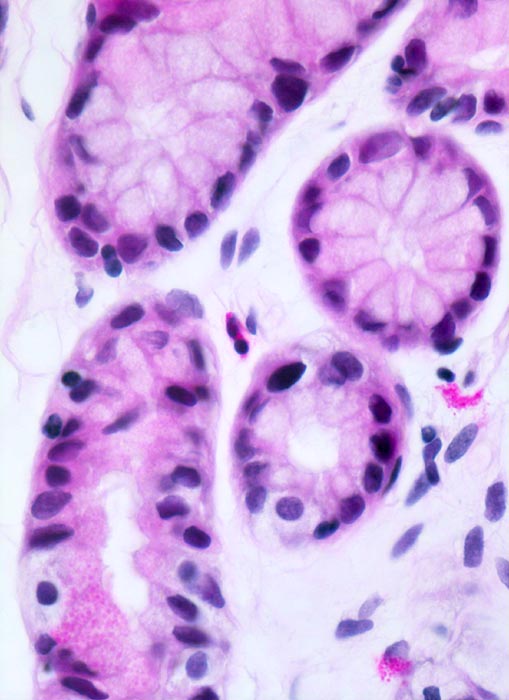

normales Magenantrum: Schleimdrüsen

Die Schleimdrüsen des Magenantrums werden ausgekleidet durch kubische bis hochprismatische schleimbildende Zellen mit eingestreuten enterochromaffinen Zellen des diffusen neuroendokrinen Systems. Diese Zellen haben helles Zytoplasma und dunkle runde Kerne. Lockeres Stroma der Lamina propria mit einzelnen eosinophilen Granulozyten. Neutrophile Granulozyten oder Plasmazellen sind nicht nachweisbar.

630